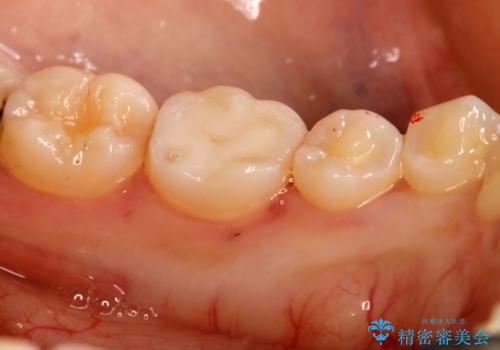

- 10年以上ぶりに歯科に来院された患者です。

口腔内・レントゲン写真からう蝕が見られたので治療を勧めたところ、自費治療を希望されたのでセラミックインレーにて治療を行いました。

左下6番のカリエス除去を行ったところ、深くまで削る必要があったため、CR裏層をした上でセラミックインレー形成をしました。